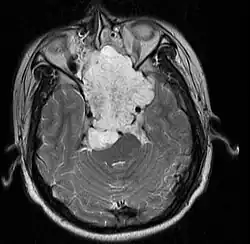

Skull Base

• Hannover; 2007 (Germany) PMID 17695386 -- "Chordomas of the skull base: surgical management and outcome." (Samii A, J Neurosurg. 2007 Aug;107(2):319-24.)

• Retrospective. 49 patients. Transethmoidal approach 36%, pterional 23%, retrosigmoid 23%.

• Outcome: GTR 49%, subtotal resection 51%. Initial surgery GTR 78%. 5-year OS 65%, 10-year OS 39%

• Toxicity: New neurological deficit 12%

• Conclusion: Chordoma cannot be regarded as surgically curable tumors, given the 5- and 10-year OS

• Institut Curie; 2005 (1992-2002) PMID 16227160 -- "Chordomas of the base of the skull and upper cervical spine. One hundred patients irradiated by a 3D conformal technique combining photon and proton beams." Noel G et al. Acta Oncol. 2005;44(7):700-8.

• Retrospective. 100 patients w/ skull base or upper cervical spine chordoma tx'd w/ proton/photon therapy. Median total dose to tumor 67 CGE.

• 2 yr local control rate 86.3%, 4 yr local control rate 53.8%.

• Multivariate analysis showed minimal dose to tumor <56 CGE and failure to encompass 95% tumor w/ 95% isodose line were independent factors for local control.